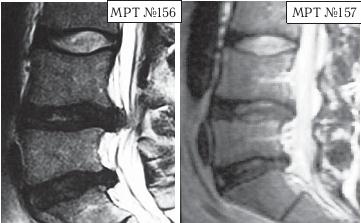

А в этом случае пациента привезли в клинику с целым «букетом» заболеваний позвоночника.

На МРТ № 156 наблюдается состояние поясничного отдела позвоночника после операций: рецидив грыжи межпозвонкового диска в сегменте LIV-LV, абсолютный стеноз спинномозгового канала на этом уровне, спондилёз, эпидурит, арахноидит, наблюдается грыжа межпозвонкового диска в сегменте LV—SI.

На МРТ № 157 — состояние поясничного отдела позвоночника после лечения методом вертеброревитологии. Обратите внимание на процессы репаративной регенерации в межпозвонковых дисках в сегментах LIV-LV и LV-SI после лечения данным методом.